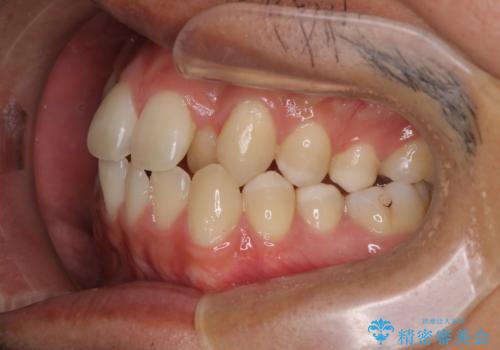

【MSE+インビザライン】前歯のガタガタ

- 前歯の凸凹を主訴に来院されました。

上の歯のアーチが狭窄していたため、骨の幅を広くするためにMSE(急速拡大装置)を使用してからインビザライン にて治療を行いました。

MSE(急速拡大装置)を用いたことで、短期間で奥歯の噛み合わせもしっかりと治すことができました。